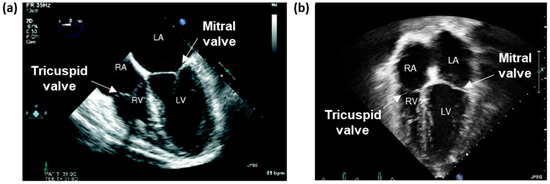

Two-Dimensional Imaging Modalities

Standard Echocardiography Imaging Windows